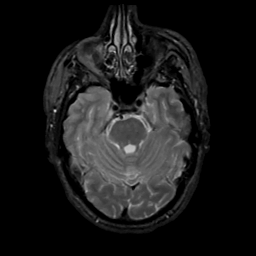

MR Study #1, February 10, 1991 -- Slice #15

[Home][Help][Clinical][Tour 1][Tour 2] Slice 15